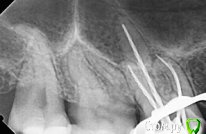

tatsiana.ma Опубликовано 3 сентября, 2017 Поделиться Опубликовано 3 сентября, 2017 Здравствуйте!Беспокоит 17 зуб, периодически возникает несильно выраженная боль, причем исключительно ночью. Врач сказал, что визуально не видит проблем. При такой симптоматике есть смысл снимать пломбу и смотреть на наличие вторичного кариеса? Боюсь дотянуть до пульпита, каналы не подарок, другую верхнюю семерку в своё время пришлось удалить, т.к. из-за сложной анатомии доп канал так и не смогли пройти.Снимки есть после лечения соседней шестерки. Ссылка на комментарий

red_butler Опубликовано 3 сентября, 2017 Поделиться Опубликовано 3 сентября, 2017 нужен очный осмотр и термо пробы хладагентом. Ссылка на комментарий